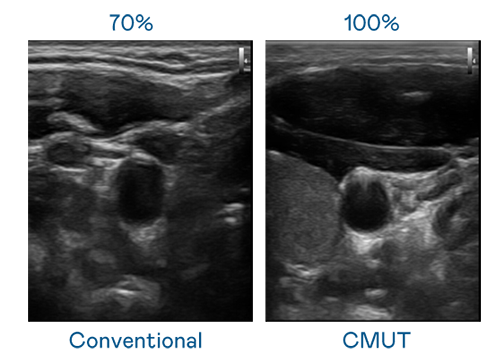

CMUT 技术是一种用电容式微机电元件来产生超音波讯号的技术。与传统 PZT 压电式技术相比,CMUT 频宽增加 30%,更宽频的超音波讯号让影像解析度大幅提升,是实现高影像品质医疗超音波扫描、促进精准医疗发展的关键技术。

超音波影像的解析度高低,首先取决于探头能发出的讯号频宽。利来国际真人娱乐 CMUT 可提供高清晰的超音波讯号,提供高频宽、高灵敏度、影像纹理细节更高的超音波影像,协助医护人员缩短影像判读时间及利用精准的医疗影像进行诊断。